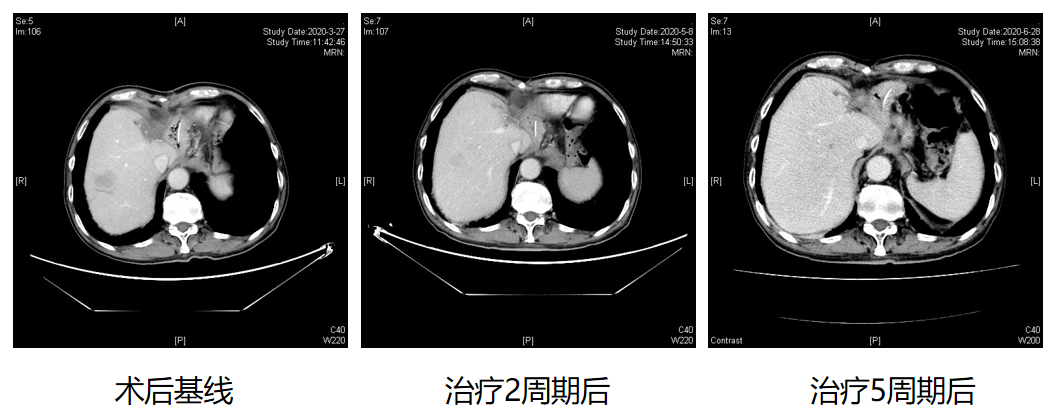

患者男性,69,工人。 患者2020-01-31因“贲门癌”和“肝癌”在我院行“全胃切除伴食管空肠Y型吻合术+左半肝切除术+解剖性肝段切除术”。术中见左肝内叶触及...